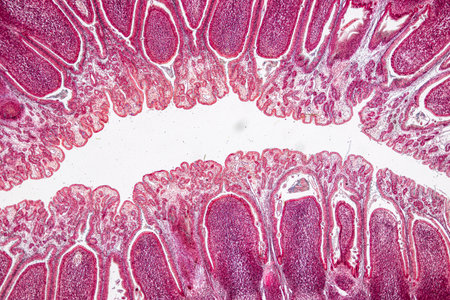

Small intestine with villi under the microscope 100x

Slow worm histology bowel transverse 100x

Cross section of intestinal glands (crypts of Lieberkühn) showing mucous goblet cells. Human colon.